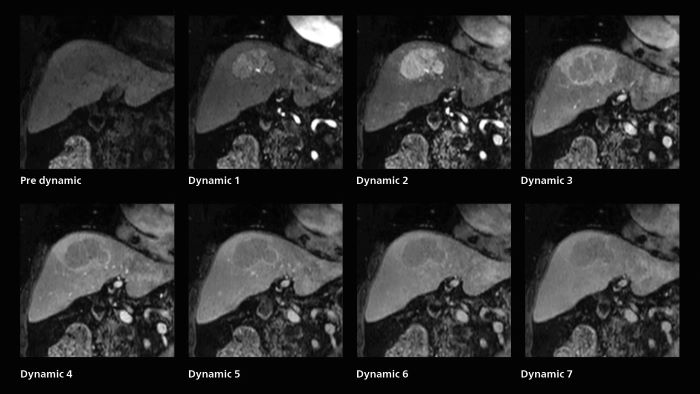

Dynamic MRI of liver using SmartSpeed

A patient was referred for MR imaging of HCC. A double arterial volume dynamic study was performed. Since it is a volume dynamic study, it can also be evaluated using MPR images. Performed on Elition X.

Fast dynamic liver MRI: volume dynamic study of 1.05 min, 1.6 x 1.8 x 2.0 mm, 200 slices

The hospital’s routine ExamCard for dynamic MRI of the liver uses total scan duration 1:05 min, dynamic scan time 9.2 sec, 1.6 x 1.8 x 2.0 mm, 200 slices, acceleration factor 8.

Also in dynamic MRI of the liver Dr. Katahira sees important improvements. While previously his scan used 9 seconds for a 5 mm slice, SmartSpeed now allows him to achieve a thin slice volume scan (1.6 x 2.1 x 2mm) with double arterial phase using acceleration factor 8. He indicates this is very useful for the radiologist when diagnosing, especially because it can provide a high temporal resolution.